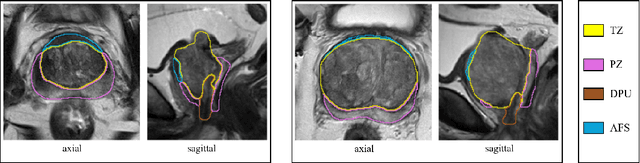

Abstract:The detailed images produced by Magnetic Resonance Imaging (MRI) provide life-critical information for the diagnosis and treatment of prostate cancer. To provide standardized acquisition, interpretation and usage of the complex MRI images, the PI-RADS v2 guideline was proposed. An automated segmentation following the guideline facilitates consistent and precise lesion detection, staging and treatment. The guideline recommends a division of the prostate into four zones, PZ (peripheral zone), TZ (transition zone), DPU (distal prostatic urethra) and AFS (anterior fibromuscular stroma). Not every zone shares a boundary with the others and is present in every slice. Further, the representations captured by a single model might not suffice for all zones. This motivated us to design a dual-branch convolutional neural network (CNN), where each branch captures the representations of the connected zones separately. Further, the representations from different branches act complementary to each other at the second stage of training, where they are fine-tuned through an unsupervised loss. The loss penalises the difference in predictions from the two branches for the same class. We also incorporate multi-task learning in our framework to further improve the segmentation accuracy. The proposed approach improves the segmentation accuracy of the baseline (mean absolute symmetric distance) by 7.56%, 11.00%, 58.43% and 19.67% for PZ, TZ, DPU and AFS zones respectively.

Abstract:Various convolutional neural network (CNN) based concepts have been introduced for the prostate's automatic segmentation and its coarse subdivision into transition zone (TZ) and peripheral zone (PZ). However, when targeting a fine-grained segmentation of TZ, PZ, distal prostatic urethra (DPU) and the anterior fibromuscular stroma (AFS), the task becomes more challenging and has not yet been solved at the level of human performance. One reason might be the insufficient amount of labeled data for supervised training. Therefore, we propose to apply a semi-supervised learning (SSL) technique named uncertainty-aware temporal self-learning (UATS) to overcome the expensive and time-consuming manual ground truth labeling. We combine the SSL techniques temporal ensembling and uncertainty-guided self-learning to benefit from unlabeled images, which are often readily available. Our method significantly outperforms the supervised baseline and obtained a Dice coefficient (DC) of up to 78.9% , 87.3%, 75.3%, 50.6% for TZ, PZ, DPU and AFS, respectively. The obtained results are in the range of human inter-rater performance for all structures. Moreover, we investigate the method's robustness against noise and demonstrate the generalization capability for varying ratios of labeled data and on other challenging tasks, namely the hippocampus and skin lesion segmentation. UATS achieved superiority segmentation quality compared to the supervised baseline, particularly for minimal amounts of labeled data.